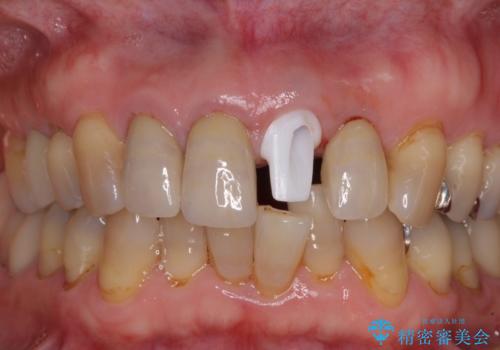

1. 折れてしまった前歯 インプラントによる補綴治療の治療前

2. 折れてしまった前歯 インプラントによる補綴治療の治療中